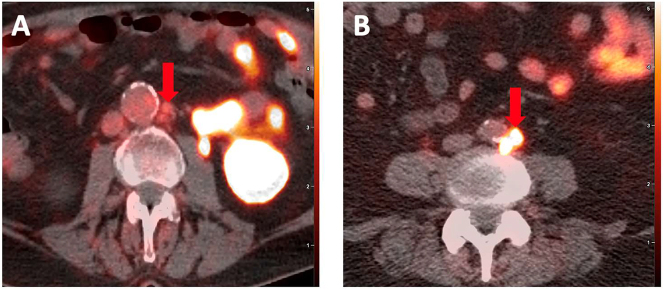

随着前列腺特异性膜抗原(PSMA)靶向正电子发射断层扫描(PET)成像技术的出现,前列腺癌(PCa)的诊断和预后发生了重大转变。与传统成像方法相比,PSMA-PET成像在检测前列腺癌、其生化复发和转移部位方面具有更高的灵敏度和特异性。这种转变现在与人工智能(AI)的快速发展——包括生成式人工智能的出现——相交叉。然而,与PSMA-PET成像相关的独特临床挑战仍然需要解决,以确保其继续广泛整合到临床护理和研究试验中。其中一些挑战是病变摄取的动态范围非常广,可能与疾病部位相邻的器官的良性摄取,训练人工智能模型的大数据集不足,以及图像中的人工制品。生成人工智能模型,如生成对抗网络、变分自编码器、扩散模型和大型语言模型,在克服各种成像模式(包括PET、计算机断层扫描、磁共振成像、超声等)的许多此类挑战方面发挥了至关重要的作用。在这篇综述文章中,我们深入探讨了生成式人工智能在增强PSMA-PET成像和图像分析的鲁棒性和广泛应用方面的潜在作用,从现有文献中吸取了见解,同时也探讨了该领域当前的局限性和未来的方向。

The diagnosis and prognosis of Prostate cancer (PCa) have undergone a significant transformation with the advent of prostate-specific membrane antigen (PSMA)-targeted positron emission tomography (PET) imaging. PSMA-PET imaging has demonstrated superior performance compared to conventional imaging methods by detecting PCa, its biochemical recurrence, and sites of metastasis with higher sensitivity and specificity. That transformation now intersects with rapid advances in artificial intelligence (AI) - including the emergence of generative AI. However, there are unique clinical challenges associated with PSMA-PET imaging that still need to be addressed to ensure its continued widespread integration into clinical care and research trials. Some of those challenges are the very wide dynamic range of lesion uptake, benign uptake in organs that may be adjacent to sites of disease, insufficient large datasets for training AI models, as well as artifacts in the images. Generative AI models, e.g., generative adversarial networks, variational autoencoders, diffusion models, and large language models have played crucial roles in overcoming many such challenges across various imaging modalities, including PET, computed tomography, magnetic resonance imaging, ultrasound, etc. In this review article, we delve into the potential role of generative AI in enhancing the robustness and widespread utilization of PSMA-PET imaging and image analysis, drawing insights from existing literature while also exploring current limitations and future directions in this domain.